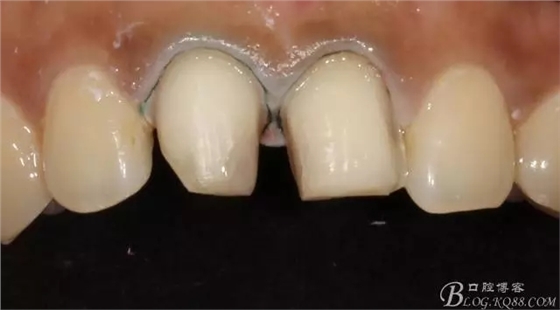

備牙后11(因扭轉(zhuǎn)制牙有點(diǎn)多,還是露牙本質(zhì)了)

局部放大